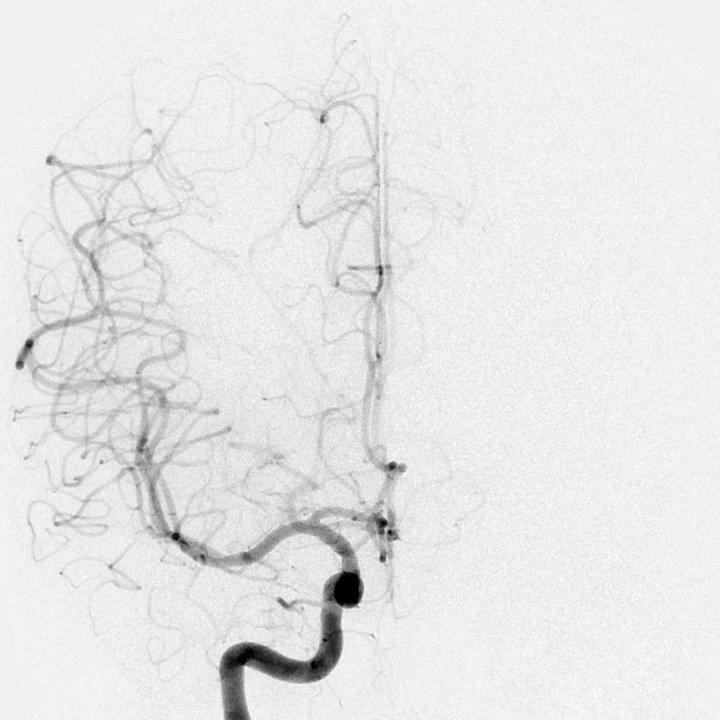

Our research seeks to advance our understanding of cerebrovascular disease and to develop new minimally invasive treatments for these diseases. We study ischemic and hemorrhagic stroke, cerebral aneurysms, delayed cerebral ischemia, cerebral arteriovenous malformations (AVMs), dural arteriovenous fistulae, and other vascular diseases of the brain. We use state-of-the-art neuroimaging techniques to non-invasively study these diseases, and we are developing future endovascular technologies to advance neurointerventional surgery.

Our clinical research team seeks to advance our understanding of ischemic and hemorrhagic stroke pathophysiology and improve the non-invasive imaging evaluation and endovascular treatment of these diseases. In addition, we are working to identify circulating biomarkers of acute and subacute cerebral ischemia to identify patients at risk of stroke before it happens.

Distinct intra-arterial clot localization affects tissue-level collaterals and venous outflow profiles

Faizy TD, et al. (2021) European Journal of Neurology. Dec;28(12):4109-4116. doi: 10.1111/ene.15079. Epub 2021 Aug 30.

Association of Venous Outflow Profiles and Successful Reperfusion After Thrombectomy

Faizy TD, et al. (2021) Neurology May 5;10.1212/WNL.0000000000012106.

doi: 10.1212/WNL.0000000000012106

Venous Outflow Profiles Are Linked to Cerebral Edema Formation at Noncontrast Head CT after Treatment in Acute Ischemic Stroke Regardless of Collateral Vessel Status at CT Angiography

Faizy T, et al. (2021) Radiology Apr 6;203651. doi: 10.1148/radiol.2021203651. Online ahead of print.

Favorable Venous Outflow Profiles Correlate With Favorable Tissue-Level Collaterals and Clinical Outcome

Faizy T, et al. (2021) Stroke Mar 8;STROKEAHA120032242.

doi: 10.1161/STROKEAHA.120.032242.Online ahead of print.